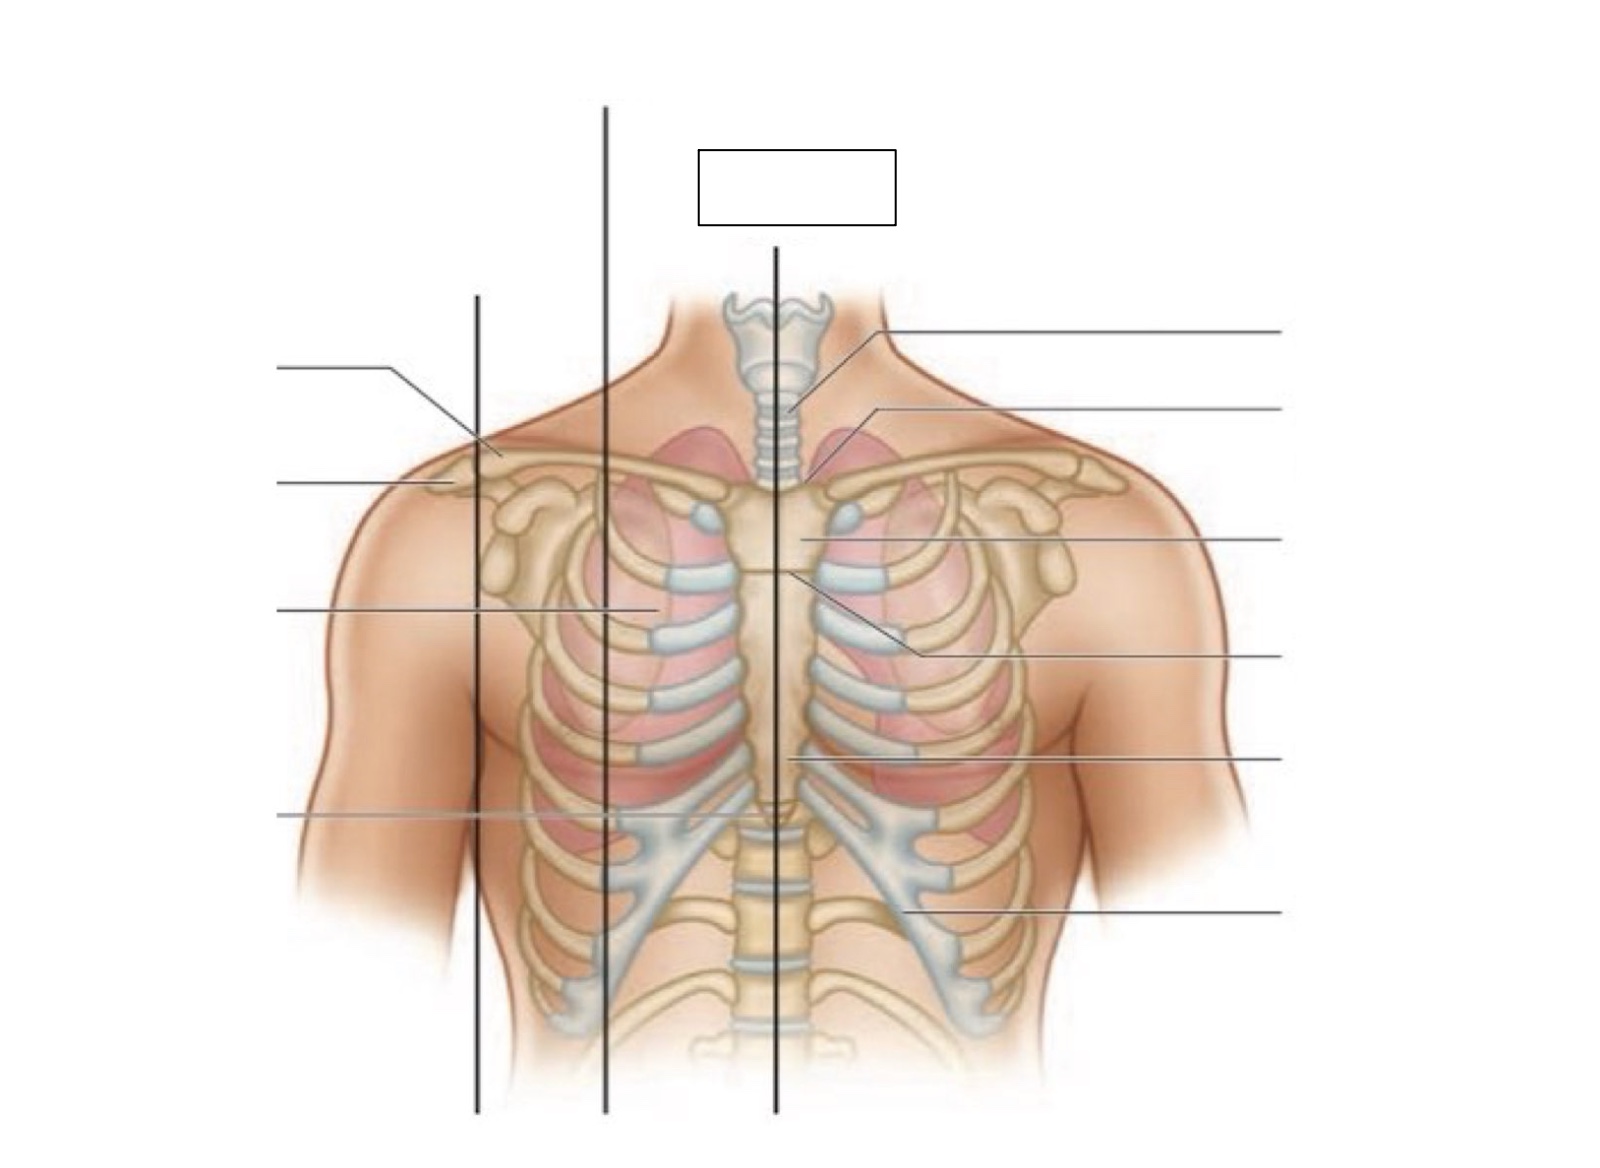

midsternal line

trachea

suprasternal notch

manubrium

angle of Louis

sternum

costal margin

xiphoid process

intercostal space

acromion

clavicle

anterior axillary line

midclavicular line

inferior angle of scapula

scapula

midscapular line

midspinal line

spinous process